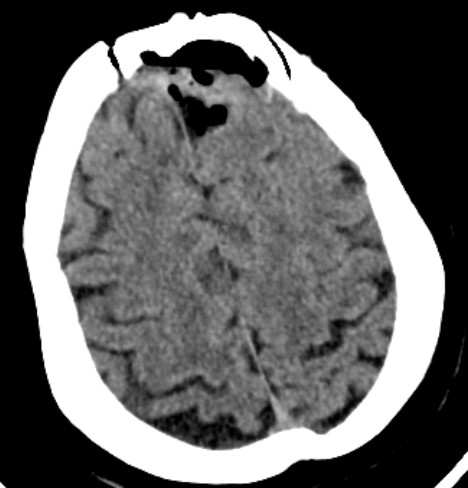

患者女性,62岁,因头晕一月在外院检查头部MR发现左额镰窦旁肿瘤来我院

完善术前检查在全麻下行左额开颅肿瘤切除术